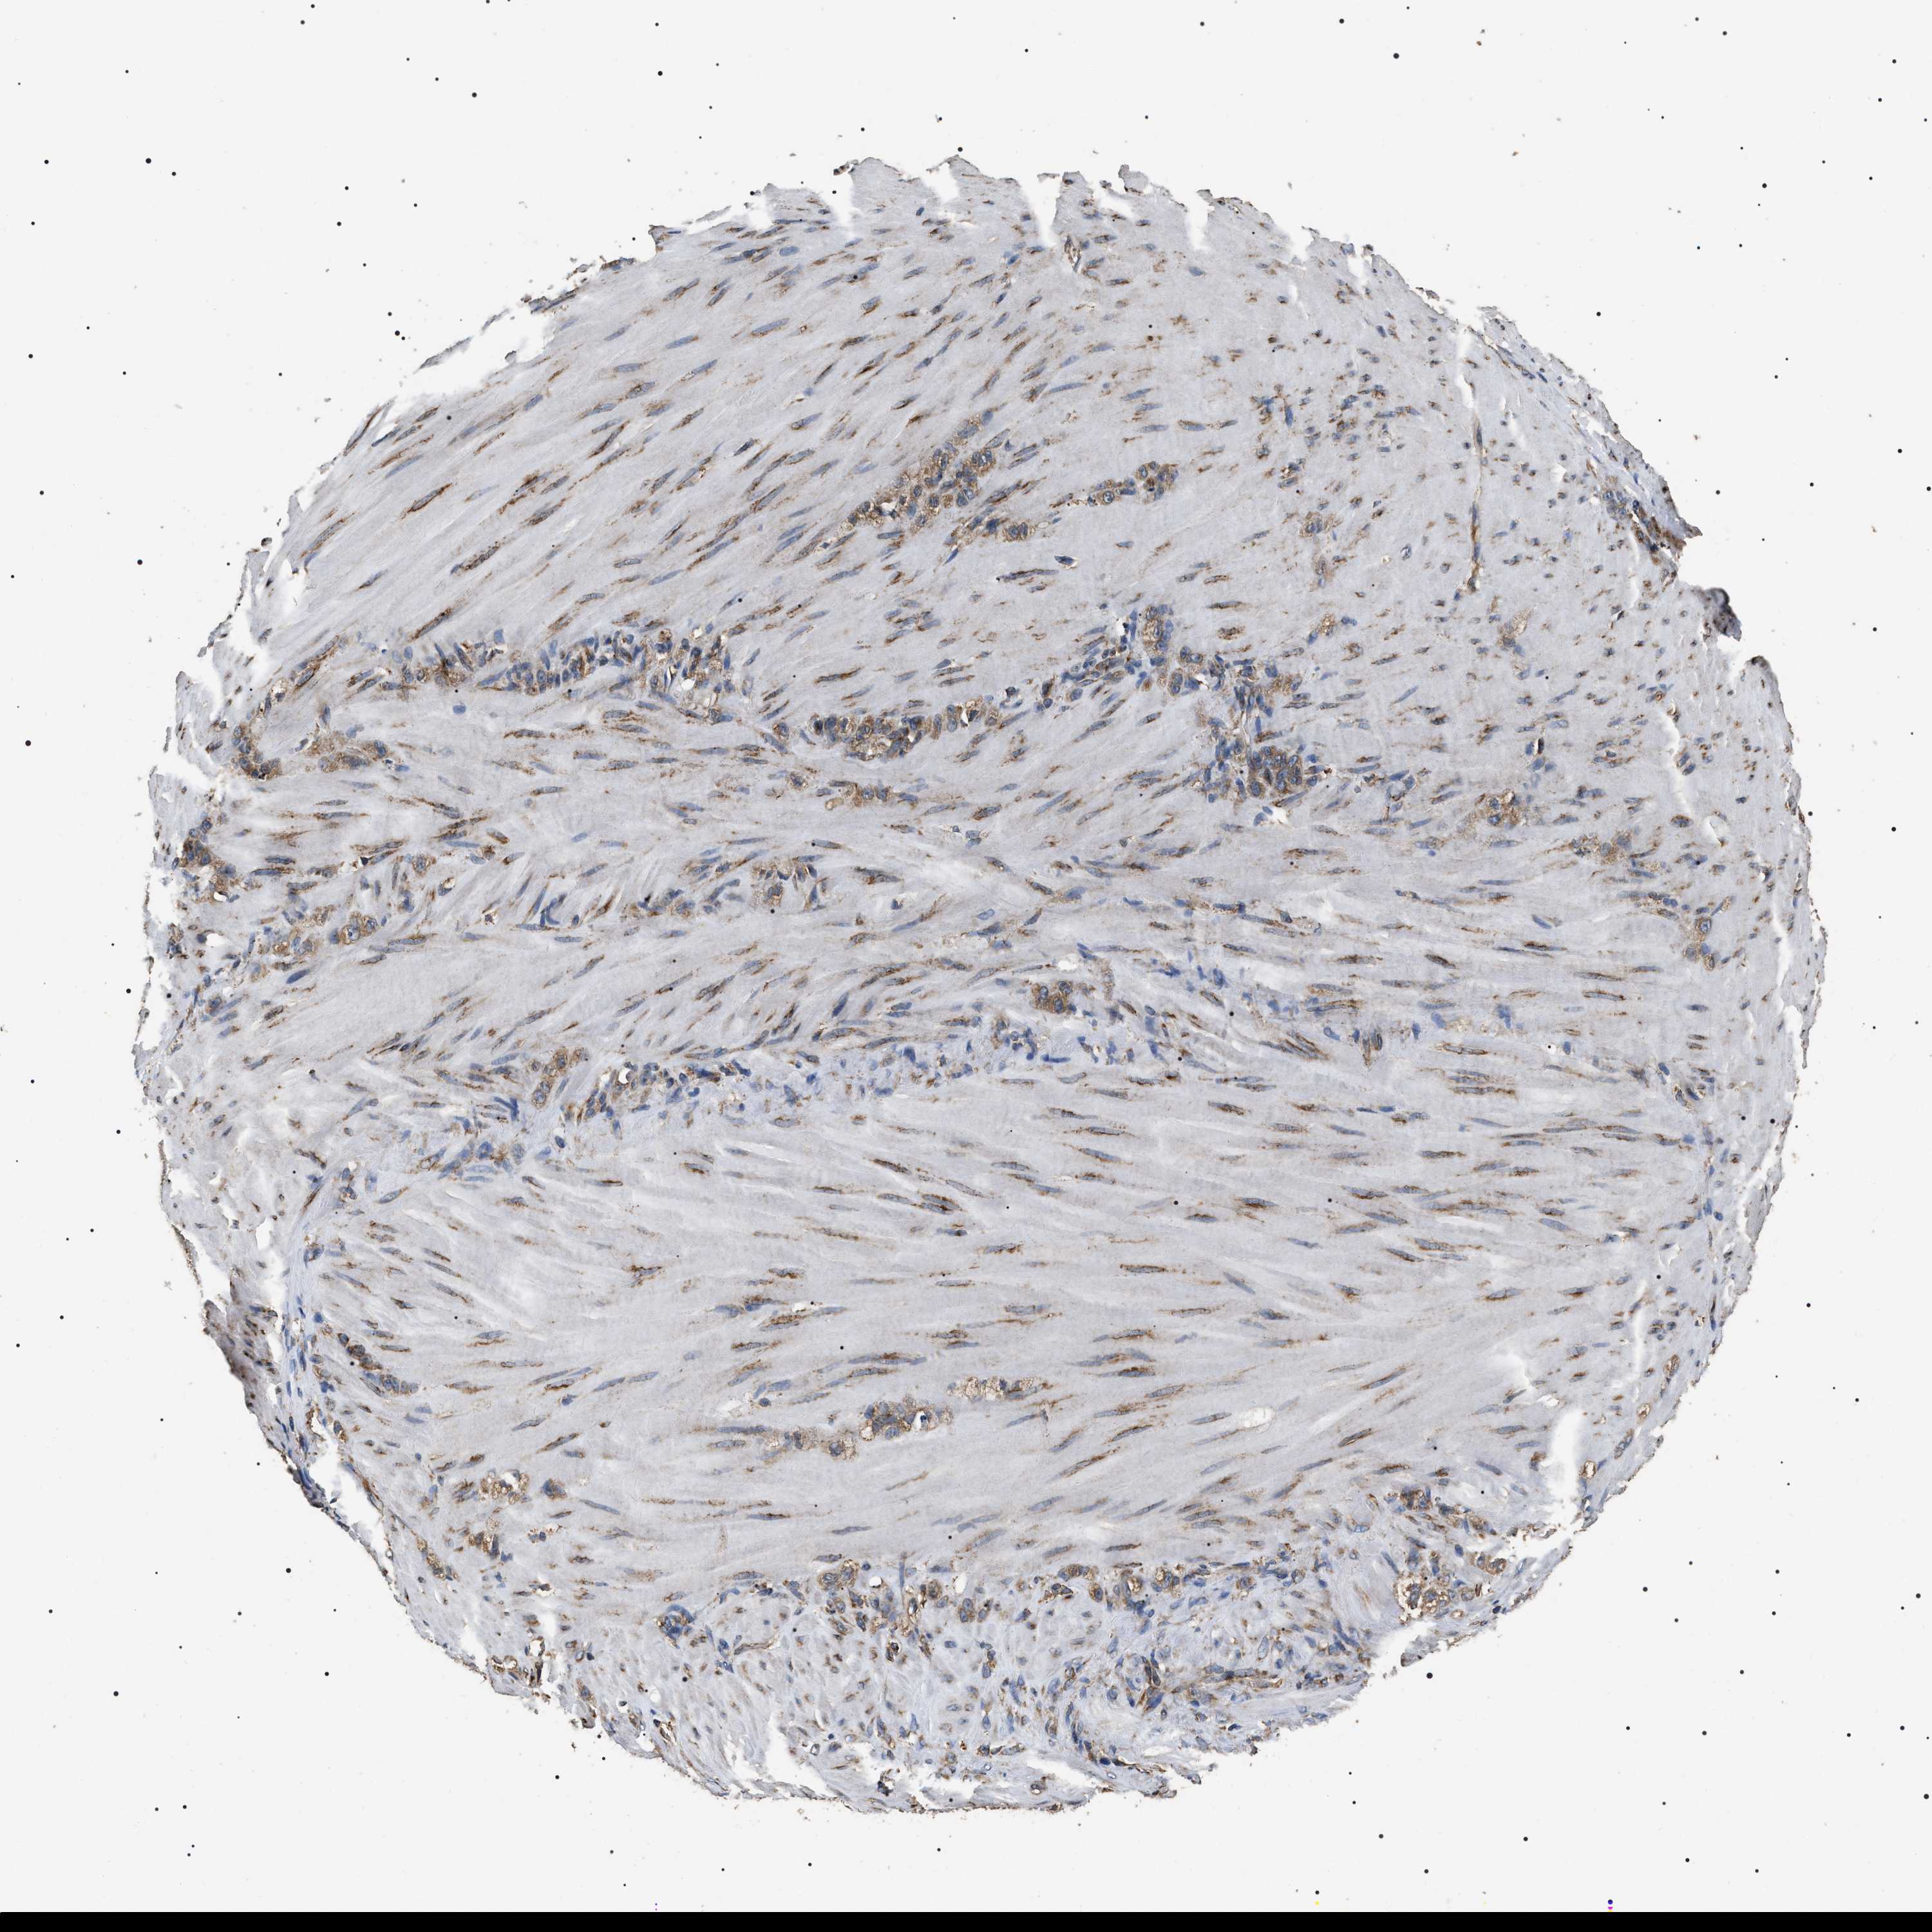

STOMACH CANCER - Protein expressioni

A mouse-over function shows sample information and annotation data. Click on an image to view it in a full screen mode. Samples can be filtered based on level of antibody staining by selecting one or several of the following categories: high, medium, low and not detected. The assay and annotation is described here.

Note that samples used for immunohistochemistry by the Human Protein Atlas do not correspond to samples in the TCGA dataset.

Antibody stainingi

Antibody staining in the annotated cell types in the current human tissue is reported as not detected, low, medium, or high, based on conventional immunohistochemistry profiling in selected tissues. This score is based on the combination of the staining intensity and fraction of stained cells.

Each image is clickable and will lead to virtual microscopy that enables deeper exploration of all samples and also displays staining intensity scores, fraction scores and subcellular localization as well as patient and tissue information for each sample.

Antibody HPA003178

Antibody HPA017876

Antibody CAB015331

Staining

High

Medium

Low

Not detected

Intensity

Strong

Moderate

Weak

Negative

Quantity

>75%

75%-25%

<25%

None

Location

Nuclear

Cytoplasmic/membranous

Cytoplasmic/membranous,nuclear

Adenocarcinoma, NOS

Adenocarcinoma, High grade